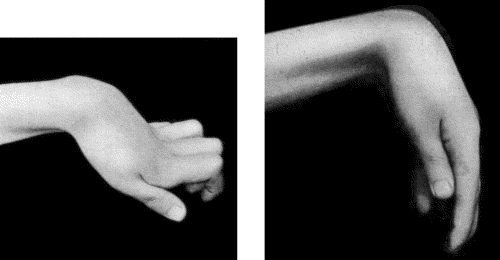

90.Drop-Wrist following Fracture of Shaft of Humerus 365

91.To illustrate the Loss of Sensation produced by Division of the Median Nerve 367

92.To illustrate Loss of Sensation produced by Complete Division of Ulnar Nerve 368